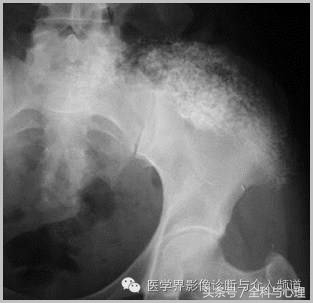

软组织钙化与骨化,软组织钙化和骨质增生 大粗隆滑囊炎